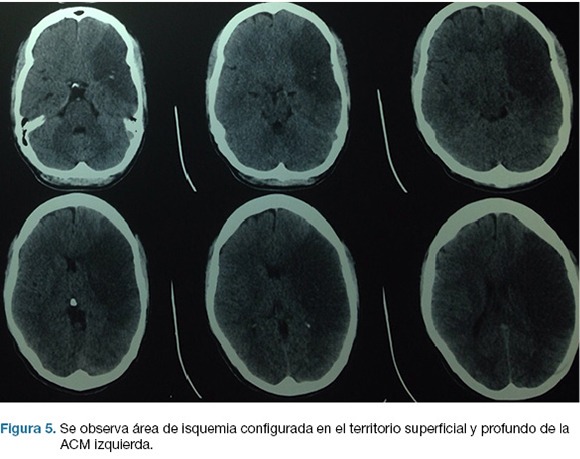

Se realiza TC de cráneo (Figura 4) y rTPA i/v. TC cráneo de control a las 24 hs sin cambios. A las 48 hs instala agravación del nivel de conciencia, apertura ocular al llamado, CGS: 9. Se repite TC cráneo (Figura 5), realizándose hemicraniectomía decompresiva de urgencia. En el post operatorio ingreso a CTI, IOT, en ARM, sin apertura ocular al llamado, gestos, localizando con miembro superior izquierdo. CGS: 8.

En la evolución agrega anisocoria izquierda que revierte con tratamiento médico. TC cráneo de control (Figura 6) evidencia agravación, por lo que se re-interviene realizándose lobectomía temporal izquierda reglada. De la evolución post-operatoria en CTI presenta CGS: 9, cifras de PIC menores de 20 mmHg, pupilas simétricas y reactivas, buena evolución. En sala paciente con mejoría de déficit motor, y de su afasia, emite palabras. Se recoloca hueso al mes de cirugía. Escala mRS al alta: 3.